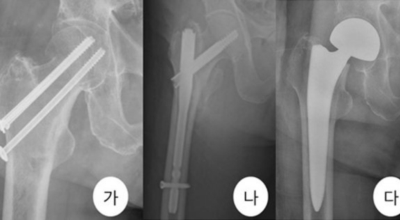

고관절 통증 치료에는 크게 약물 치료와 물리 치료가 있답니다. 고관절염의 진행을 늦추거나 증상을 개선하기 위한 목적으로 항염증제 또는 진통제를 투여해요. 고관절 질환의 일부 증상은 체외 쇼크파, 물리치료, 약물치료 과 같은 비수술 요법으로 증상이 호전될 수 있습니다.

그러나 비수술 치료법으로 개선시키는 것이 어려운 경우 수술적 방법이 고려되어요. 고관절 통증을 조기에 치료하면 약물치료 외에 물리치료로 약 50% 정도 큰 효과를 볼 수 있답니다. 게다가, 보통 고관절 증상 관리에 보탬이 되는 요가, 수영, 스트레칭은 고관절 예방과 치료에 보탬이 돼요.